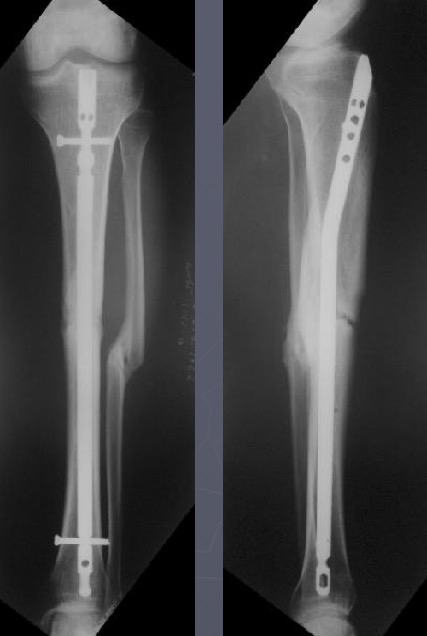

Вложение не в текстовом формате было извлечено&hellip;

Имя     : Снимок экрана 2018-03-31 в 8.39.03.jpg

Тип     : image/jpeg

Размер  : 40988 байтов

Описание: отсутствует

Url     : http://weborto.net:8080/pipermail/ortho/attachments/20180331/6be0b812/attachment-0005.jpg